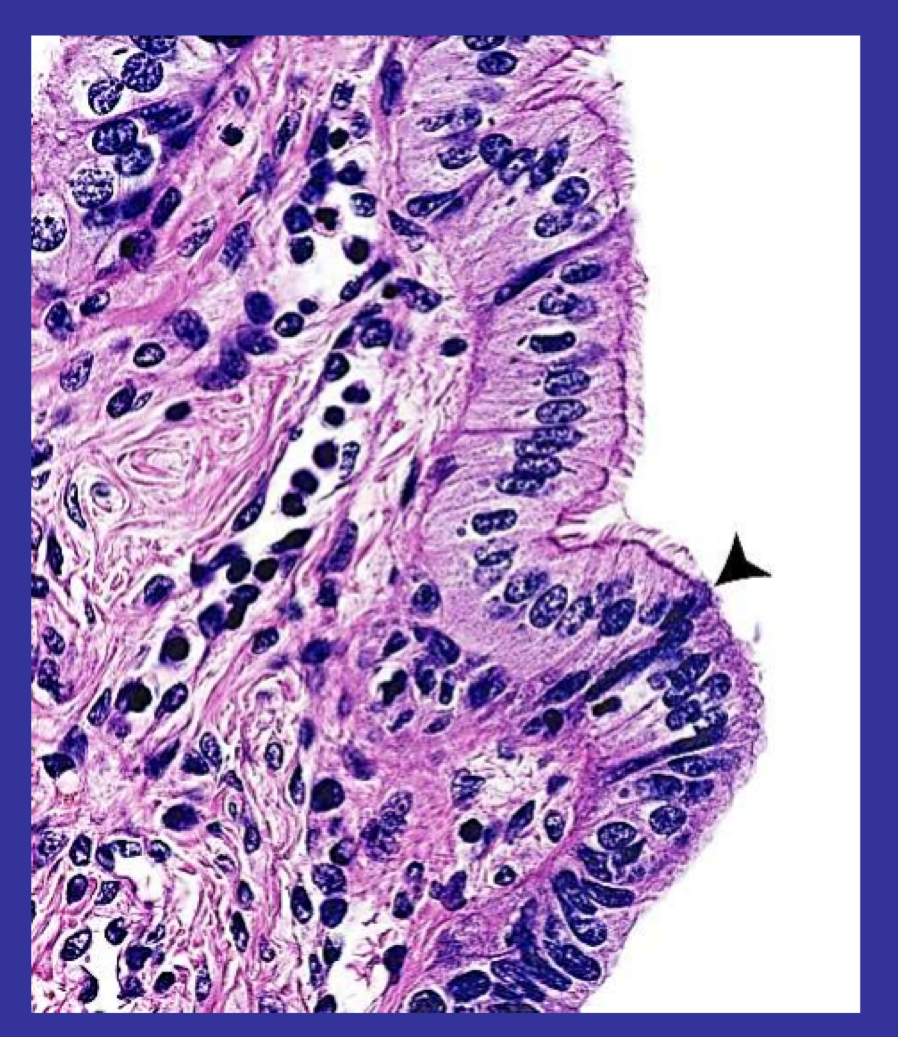

What type of epithelia is this and from which structure do they come from?

Simple columnar epithelium lining the fallopian tube of the uterus

Some cells are cilliated (see arrow)